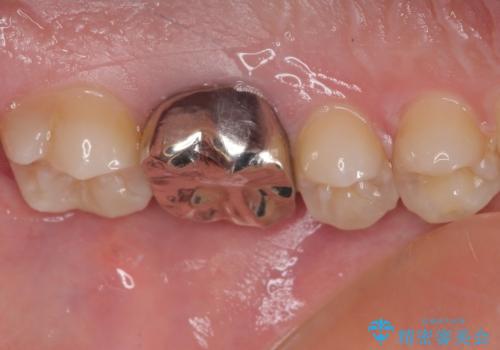

右下の銀の詰め物は、外してむし歯を除去した後、セラミックインレーにて修復することとしました。

左上の銀歯は、銀歯の下に金属の土台が入っているため、その土台を除去し、ファイバーコアにやり替えて、オールセラミッククラウンにて補綴することとしました。